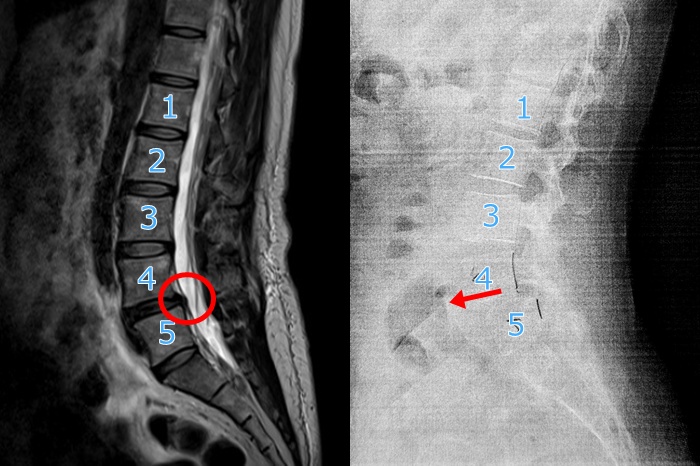

さっきふと思ったのだけど、私の脊椎のすべりって2022年の時からあったんだろか?それとも関節リウマチになってからすべったんだろか?確か2022年のMRIのデータがPCにあったはず、と探したらありました!

MRIとレントゲンなので姿勢も違うし椎間板や神経が写ってたり写ってなかったりしますが、骨の比較はできそうなので並べてみたところ

(左)2022年6月 (右)2026年1月

あーなんか違いますねぇ。左が2022年のMRIね。2022年も若干すべり始めてる気がしないでもないけど、やっぱり今回の4番は明らかに前に出てるっぽい。

2022年のときも左足がビリビリしびれて痛くなって、〇で囲んだところの椎間板が少し神経を圧迫してるので『椎間板ヘルニアぎみ』と言われてました。今ってどうなってるんだろう?リウマチのせいなのか加齢のせいなのかわからないけど、神経がぐにゃって曲がってるのかと思うとなんか考えただけで痛くなってきました。